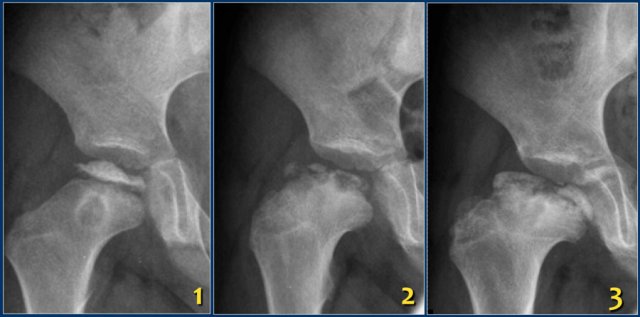

Early radiographs may be normal or show subtle flattening of the femoral head. Sclerosis and subchondral fractures may develop, features best appreciated on the frog-leg lateral view.

The images show Perthes disease of the right hip in a five-year old boy.

The findings are:

- Flattened and sclerotic femoral epiphysis.

- Subcondral fracture, best appreciated on the frog-leg lateral view.

The images show:

- Collapse and sclerosis of the femoral head and metaphyseal lucency.

- Progression to fragmentation and development of a short, broad collum.

- Developing coxa magna deformity.